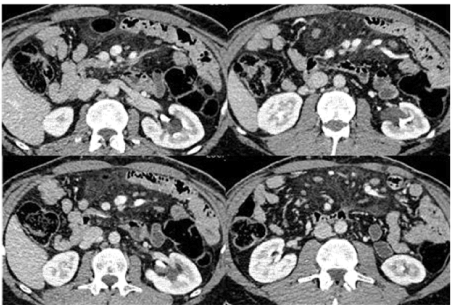

Figure 2. Axial Images: CT urogram was advised to exclude stone. CT urogram shows no hydro nephrosis. No stone in kidneys, ureters and urinary bladder. Re-demonstration of cystic structures from left renal pelvis extending alongside of calyceal system.

Figure 3. Axial Images: CT urogram was advised to exclude stone. CT urogram shows no hydro nephrosis. No stone in kidneys, ureters and urinary bladder. Re-demonstration of cystic structures from left renal pelvis extending alongside of non-dilated calyceal system. Incidentally noted mesenteric root fat stranding with multiple lymph nodes, representing mesenteric panniculitis. Non-contrast study for comparison.